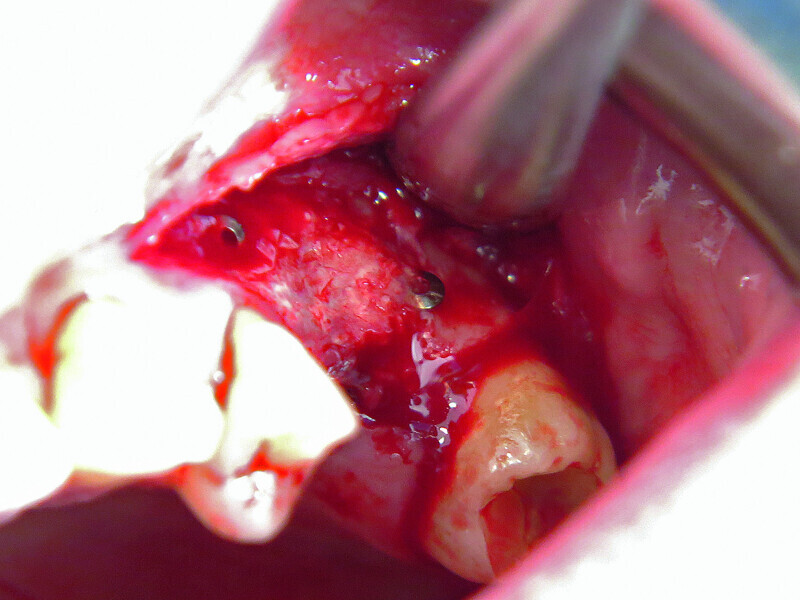

Fig. 2: Micro-osteoperforation in order to enhance bone formation.